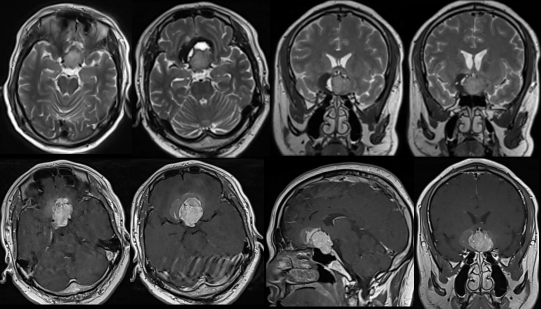

术前影像资料